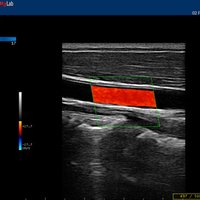

12”-Full-Touchscreen Farbdoppler

Das MyLab™One steht für das revolutionäre „Arm-held“ Hochleistungs-Ultraschallsystem mit 12”-Full-Touchscreen. Aufgrund seines geringen Gewichts und der Tragbarkeit kann es auch ohne Arbeitsfläche verwendet werden. Eine einzelne Person kann dieses Gerät aufgrund seiner einzigartigen Funktionen allein und selbstständig bedienen.

Das Ultraschallsystem MyLab™One zeigt exemplarisch den modernen Bedarf an Diagnosekapazitäten in verschiedenen Anwendungsbereichen: Radiologie, Kardiologie, Phlebologie, Frauenheilkunde, Orthopädie, Regionalanästhesie, Sportmedizin, Interventionell, Rheumatologie, Erste Hilfe, Notfallmedizin, Vaskuläre Reihenuntersuchungen, Allgemeinpraxis.

• Features: Farb/Doppler, Nadelführung, SW/B-Bild